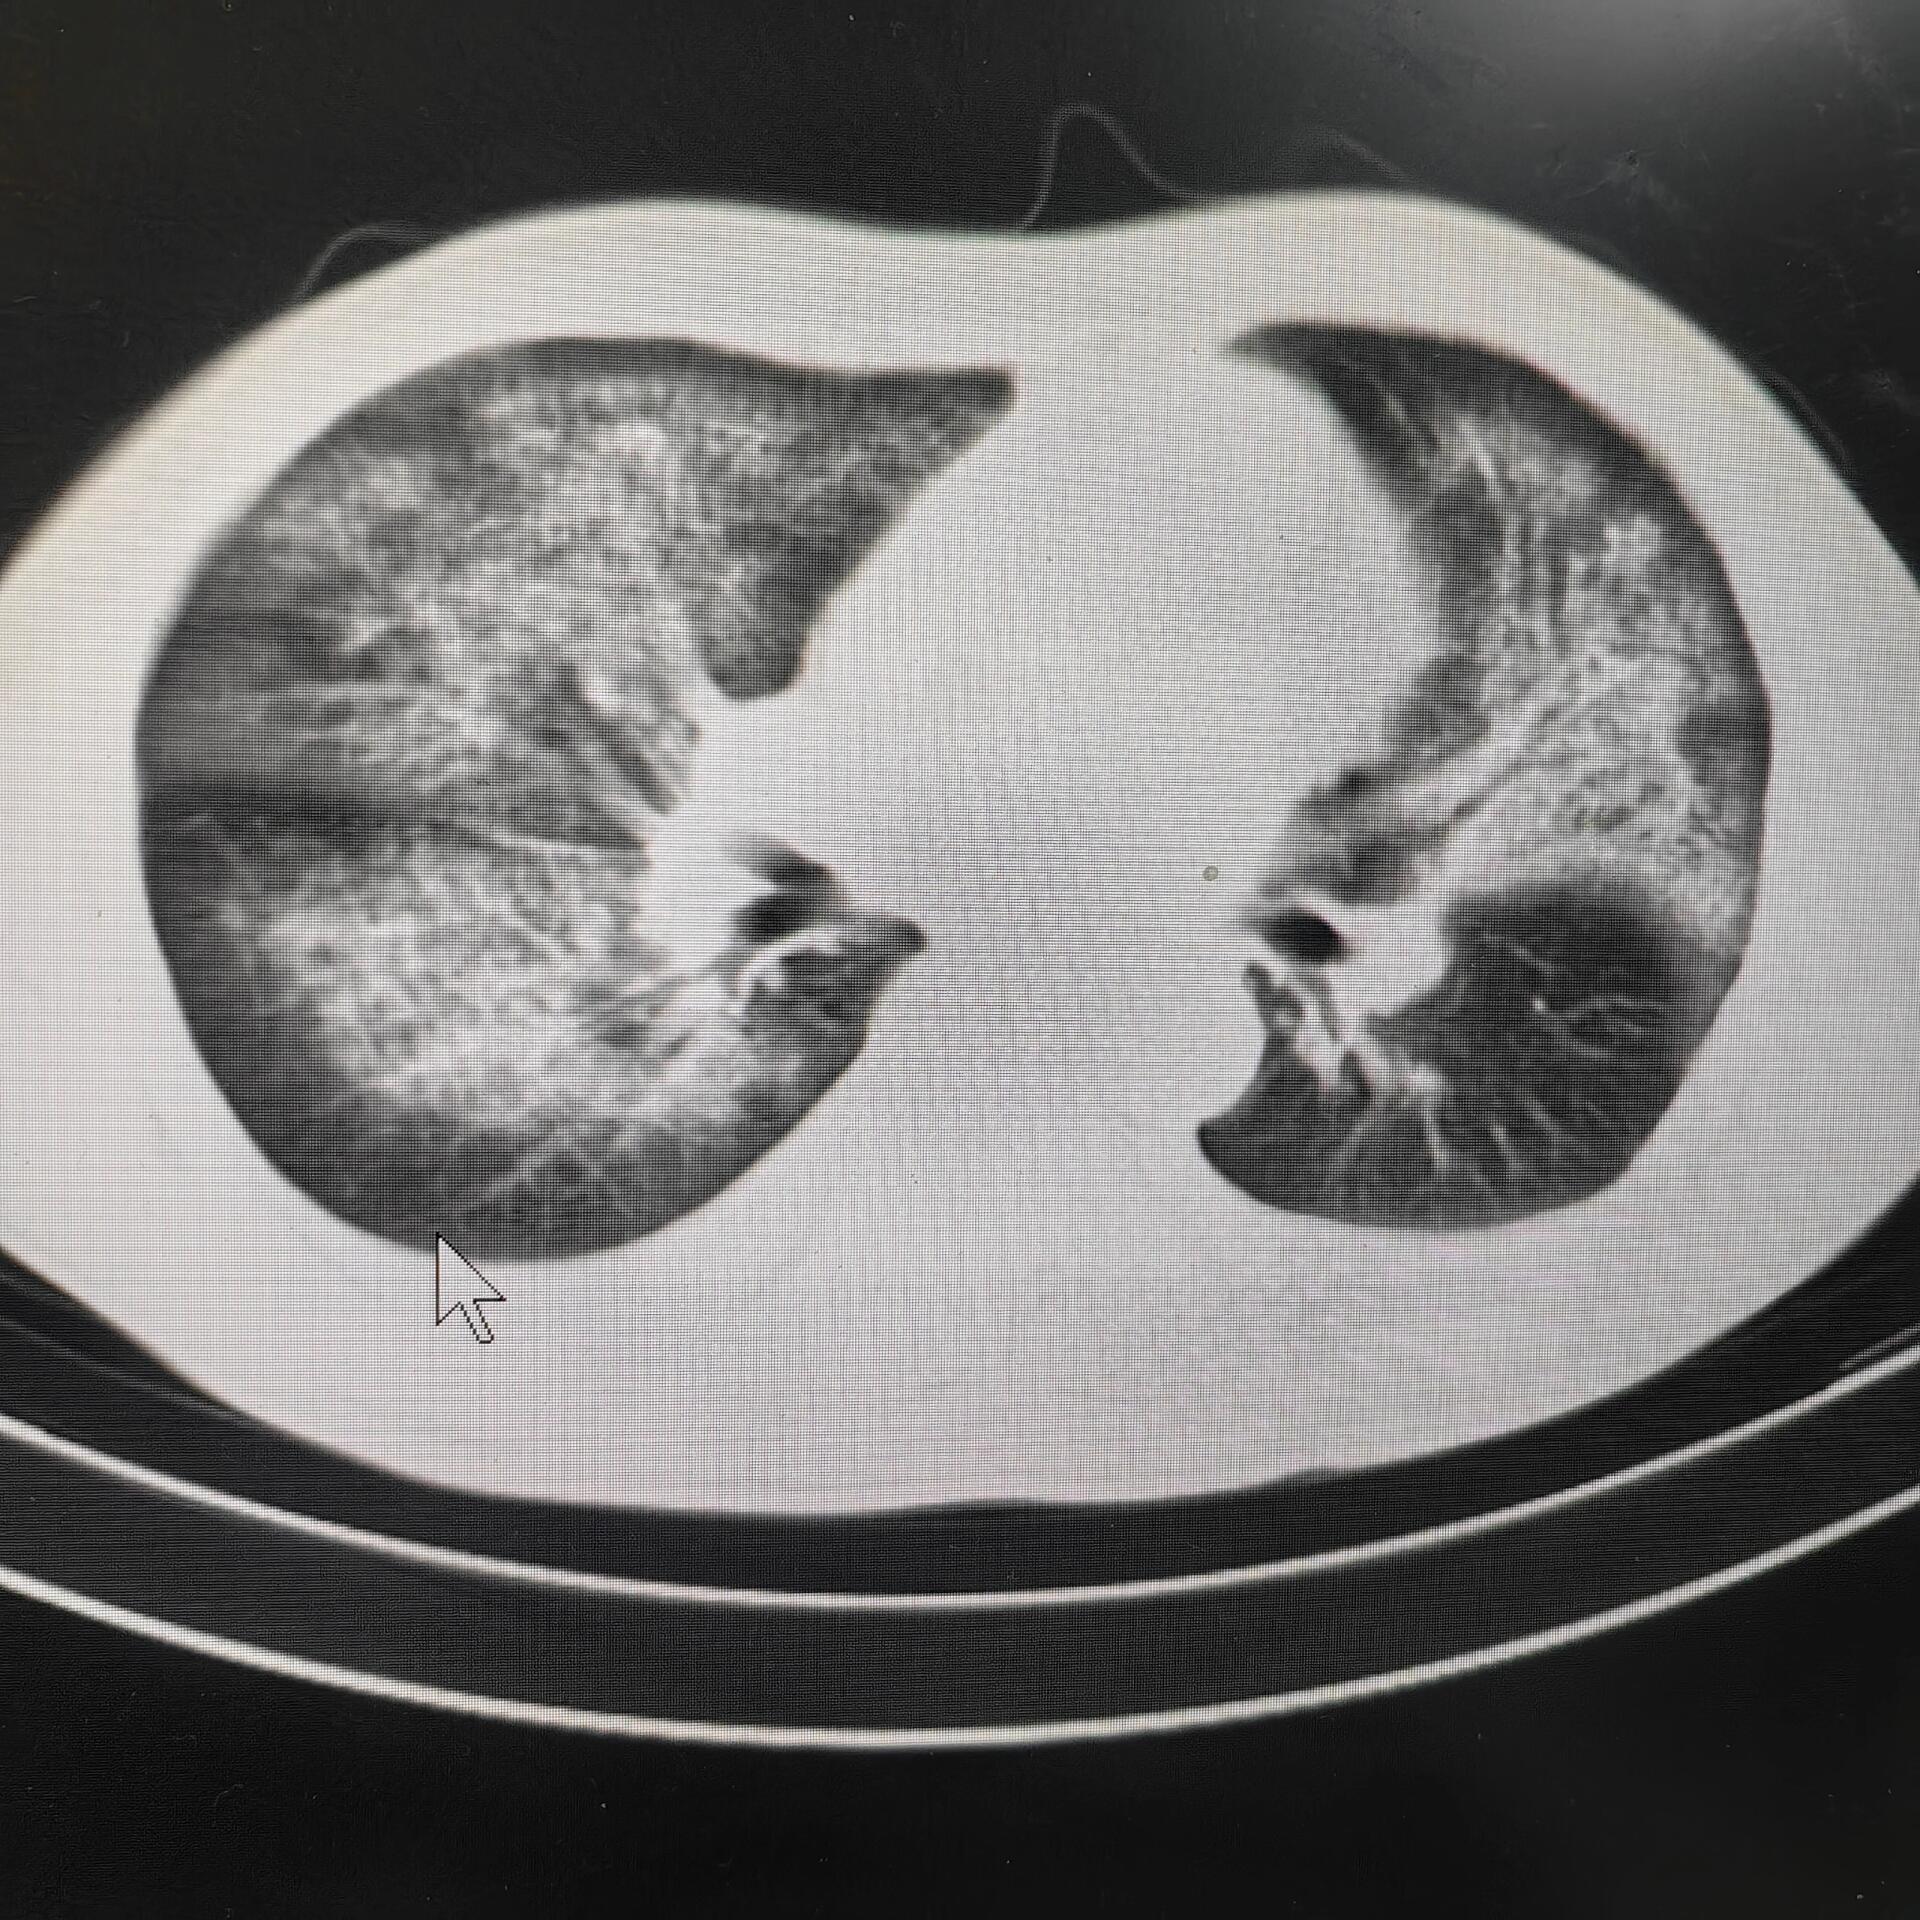

男性57岁,咳嗽,咳痰半月,肺脓肿猜病原体